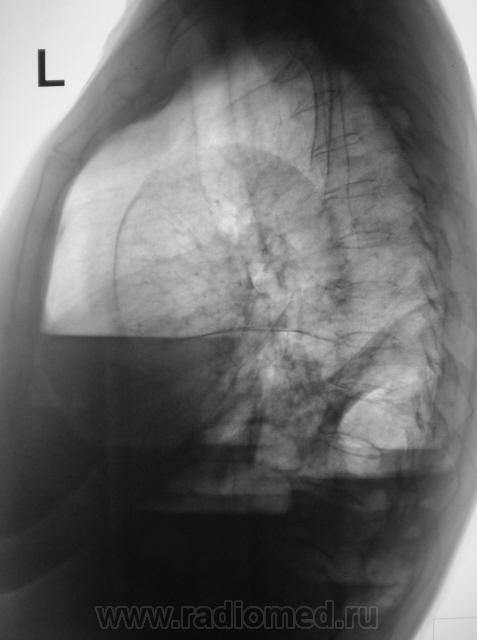

Понял. Гнойное расплавление легкого, множ. абсцессы. Когда-то был у меня такой случай: на прямой 1-2 уровня. Не хотел делать боковой, мол и так все ясно. А на боковом - целые аркады.

Травмы не было, и брюшной полости в том числе. Пациентка в течение 1 месяца "народными средствами" лечилась от "простуды". Но темперетура поползла и бабушка обратилась в больницу, участковым терапевтом была направлена на рентгенографию - 1 снимок.

После производства снимка (ургентном порядке), по-сему снимок в одной проекции, так как терапевт, аускультативно ничено не услышал, заказал только прямую проекцию, а лаборант и сделал одну проекцию.

Пациентку весьма интенсивно начали лечить в терапии, но стало хуже пациентке, начала "качать жидкость", справа, кроме всего прочего зарегистрировали пневмоторакс, был вызван их области торакальщик, который спунктировал около 3 литров справа, но с собой в область не взял, думал, по всей видимости, что "бабулька" загнется - вторая серия снимков.

Далее поключились хирурги, поставили дренаж и "бабушка" потихоньку стала выкарабкиваться - третья серия снимков, и даже начала ругаться, что чувствует себя уже хорошо, а мы тут её держим. Но её конечно "пользовали" еще, и в пятницу - последняя серия снимков - дали на контроль.